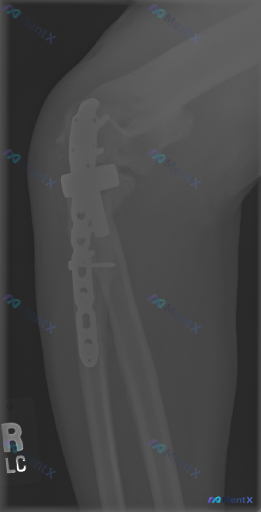

整理了一份肘关节术后的侧位X光影像分析资料,先不直接给结论,大家一起来看看读片思路。 影像基本情况 - 标记为左侧(L)肘关节侧位片 - 可见肱骨远端、尺骨近端的金属内固定系统(钢板、螺钉),还有串珠状高密度缝合钉影 - 术区有金属伪影干扰 - 局部可见骨密度增高区域(考虑骨痂形成迹象) - 目前未...

整理到一份影像读片资料,觉得很适合讨论临床思维里的“小陷阱”。 先不说结论,只看原始情境:有人拿到这张影像,第一定位错了,后面的分析全偏了。再仔细看,还有个更大的问题——金属伪影把关键区域挡住了,看似“没明显异常”,其实什么都没法确定。 大家觉得: 1. 拿到这类带内固定的复查片,第一步最应该先确认...